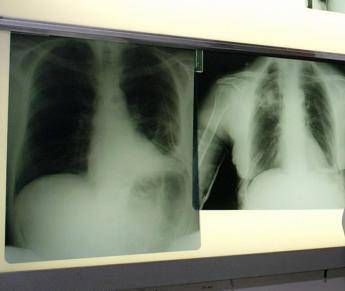

Il tumore al polmone – ricorda l'azienda in una nota – continua a essere una delle neoplasie più diffuse e letali in Italia e nel mondo. Ogni anno, solo in Italia, vengono diagnosticati 44.831 nuovi casi. Circa il 12% riguarda il carcinoma polmonare a piccole cellule, una forma aggressiva e a rapida progressione, per la quale le opzioni terapeutiche sono rimaste a lungo limitate. Negli ultimi anni, tuttavia, i progressi nel trattamento dello Sclc hanno aperto nuove prospettive. Tra questi, un composto sintetico di origine marina – estratto dall'invertebrato Ecteinascidia turbinata – che ha dimostrato risultati promettenti in combinazione come terapia di mantenimento in prima linea per i pazienti con Sclc in stadio esteso (Es-Sclc), una delle forme tumorali più aggressive e con maggiori bisogni clinici insoddisfatti. Come dimostrano i risultati dello studio di fase 3 IMforte, presentato lo scorso giugno all'Asco Annual Meeting 2025 di Chicago, il Congresso dell'American Society of Clinical Oncology, il composto sintetico di origine marina, in combinazione con immunoterapia, riduce del 46% il rischio di progressione della malattia o di morte, con una sopravvivenza mediana globale di 13,2 mesi rispetto ai 10,6 mesi con la sola immunoterapia. "Il carcinoma polmonare a piccole cellule è una delle forme più aggressive e difficili da trattare di tumore del polmone – spiega Silvia Novello, direttrice della Struttura complessa a direzione universitaria di Oncologia medica dell'Ospedale San Luigi di Orbassano e professoressa ordinaria di Oncologia medica all'Università degli Studi di Torino – Nella maggior parte dei casi, la diagnosi avviene quando la malattia è già in fase avanzata e le opzioni terapeutiche a disposizione sono limitate. I risultati dello studio IMforte rappresentano un'importante novità: la nuova combinazione ha dimostrato un beneficio clinico significativo, con un miglioramento della sopravvivenza globale e della sopravvivenza libera da progressione. Si tratta di dati estremamente incoraggianti – sottolinea – che potrebbero cambiare concretamente l'approccio terapeutico per questi pazienti e aprire una nuova prospettiva di trattamento per una popolazione finora e per troppo tempo priva di alternative efficaci".